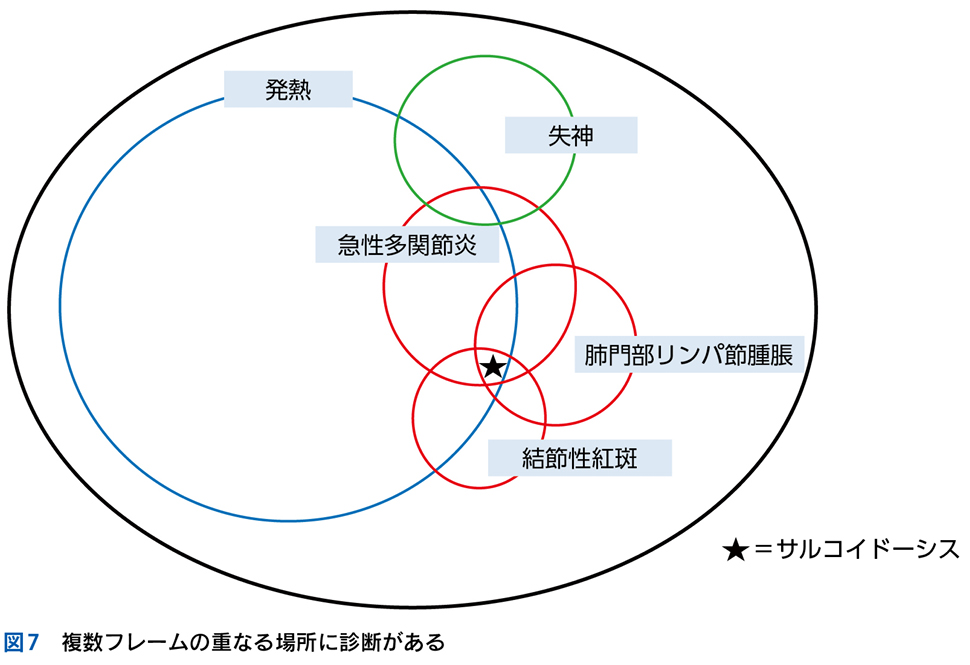

▶ 症例によっては,ここまで述べたような条件を満たす問題を複数定義できることがある。この場合は,それぞれの問題が描くフレームが重なり合うところに診断があると考えるとよい(図3)。

▶ 再びNew England Journal of Medicine誌上の症例検討3)を例として挙げる。40歳代男性が急性多関節炎,下腿の結節性紅斑,両側肺門部リンパ節腫脹を呈したケースである。これら3個の問題の組み合わせは,知っていればLöfgren症候群というサルコイドーシスの1病型と「スナップ診断」できるが,この知識がなくてもフレームの重ね合わせで診断に至ることが可能である。

▶ これらの問題はそれぞれが比較的high yieldであり,よいフレームとなりうる。3つのフレーム内でそれぞれ網羅的に鑑別を挙げ(その方法はステップ②で後述),重なるところに着目するとサルコイドーシスが診断の第一仮説に浮上する。ちなみにこのケースでは患者は発熱と失神も呈しているが,発熱はlow yieldであり鑑別を減らすのに役立たず(急性多関節炎,結節性紅斑,肺門部リンパ節腫脹を呈する疾患はほぼすべて発熱を呈してもおかしくない),失神はこのケースでは最終的に(心サルコイドーシスに起因するものではなく)発熱下での神経調節性失神という評価となり,サルコイドーシスの診断においてはノイズだった(二元論で説明される症状だった)ことがわかる(図7)。